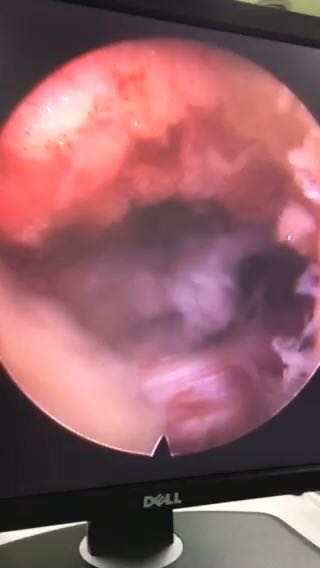

椎间孔镜下腰5骶1椎板间隙入路髓核摘除术

诊断:腰5骶1椎间盘突出症 治疗方案:椎间孔镜下经椎板间入路髓核摘除术

术后患者疼痛完全消失